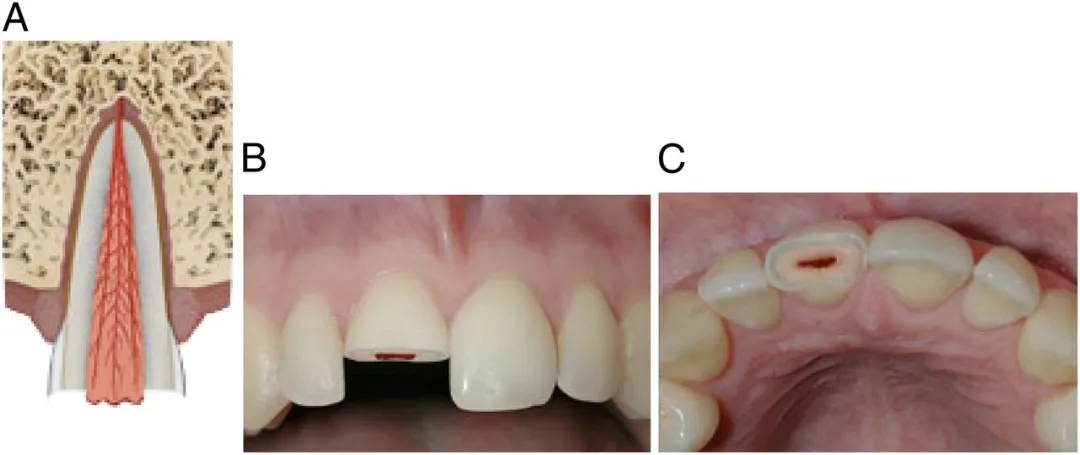

如果牙齿断得比较靠近牙根,或者摔裂了,裂缝延伸到牙根,这些情况可能会伤到牙神经,处理起来复杂一些。

为了防止牙神经感染,牙医通常采用一些材料,覆盖到这个露出神经的表面,然后再用材料把牙齿外形严密封闭。

如果牙齿磕断时间较长,露出的牙神经比较多,就采取牙髓切断术把受感染的这一部分牙神经去掉,把健康的牙髓保留下来,让牙根继续生长和发育。